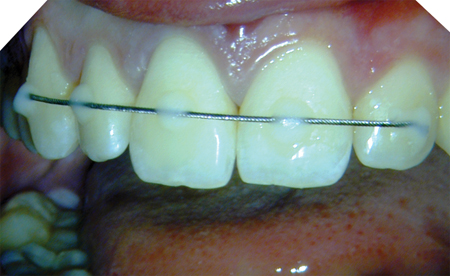

Rotary vs Reciprocation: “How Do I Choose?”

West Figure 1C alternate text for this image

IntroductionAs a practicing endodontist and a clinical endodontic educator for more than 30 years, the most frequent question I am asked about technique is, “Is it predictable?” While every dentist wants his or her endodontic treatment to be easier, more efficient, simpler, and profitable, in the end, it is predictability that trumps all considerations. As … Read more